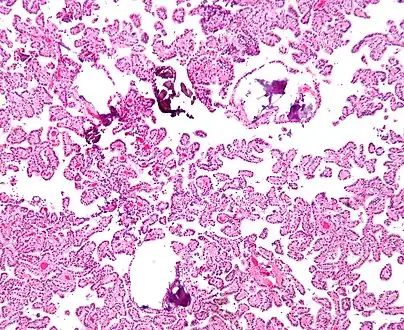

The tumor is neuroectodermal in origin and similar in structure to a normal choroid plexus. They may be created by epithelial cells of the choroid plexus.

- Micrograph of a choroid plexus papilloma. H&E stain.